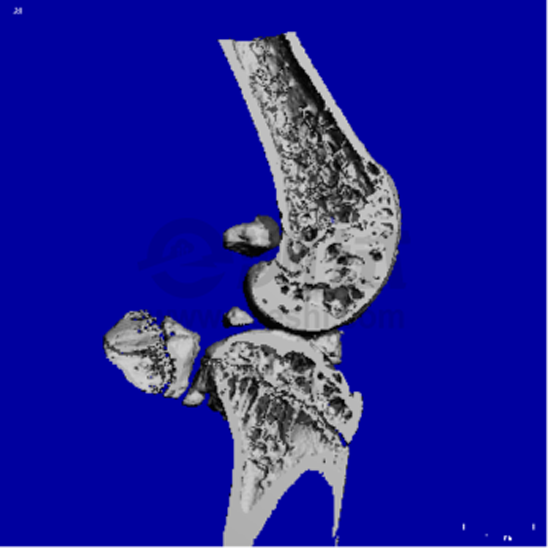

4.關(guān)節(jié)炎小鼠膝關(guān)節(jié)三維重建

00002